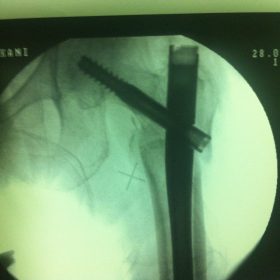

Υποκεφαλικό : Είναι ενδαρθρικό κάταγμα στον αυχένα του μηριαίου (το εσωτερικό του αρθρικού θυλάκου), το οποίο διακόπτει την αιμάτωση της κεφαλής του μηριαίου και οδηγεί σε μη πόρωση του κατάγματος (ΟΣΤΕΟΝΕΚΡΩΣΗ της Μηριαίας κεφαλής). Σε ασθενείς κάτω των 65 ετών αντιμετωπίζεται χειρουργικά με κοχλίωση στις πρώτες 12 ώρες. Τρείς βίδες σε σχήμα Τ με την βοήθεια τηλεόρασης διαδερμικά χωρίς διάνοιξη. Σε ασθενείς από 65-75 ετών γίνεται ολική αρθροπλαστική και σε ασθενείς άνω των 75 ετών αλλάζεται μόνο η κεφαλή χωρίς την αλλαγή της κοτύλης. Ο ασθενής περπατάει άμεσα μετεγχειρητικά στις 5 ώρες και εξέρχεται από το νοσοκομείο σε 1 -2 ημέρες. Στην κοχλίωση μπορεί να εξέλθει και την ίδια ημέρα.